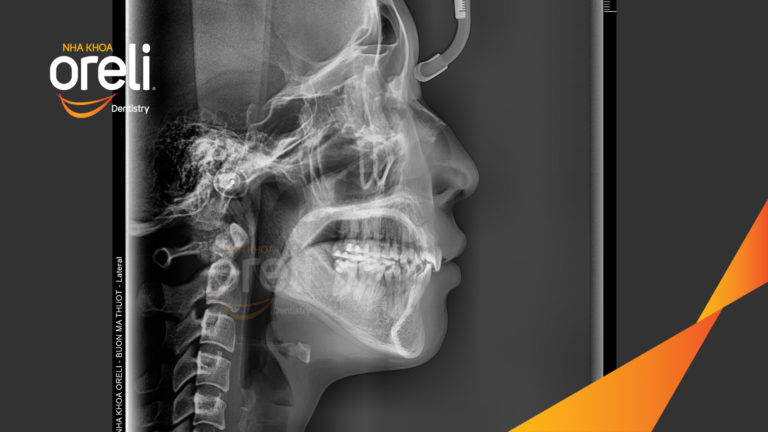

Ca chỉnh hô có nhổ 4 răng 4 thay đổi góc nghiêng đẹp – Kết quả thay đổi sau 3 năm tại nha khoa Oreli Niềng răngHô Xem thêm

Ca niềng chỉnh hô nhổ 2 răng 4 hàm trên di gần răng 7 8 hàm dưới cho nụ cười đẹp – Kết quả sau hơn 2 năm ở Oreli Niềng răngDi gần răng 7 8Hô Xem thêm